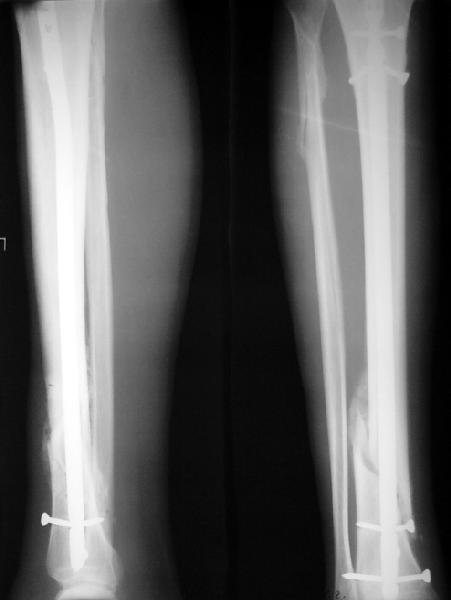

Ok. А также и следующий, в 3 месяца.

Это наглядная демонстрация возможности ранней полной нагрузки при нестабильном по оси повреждении, причем не в самых благоприятных механических условиях - при плохом сопоставлении, со слабым фиксатором.

Как я уже говорил, мы сделали выводы из этого и других подобных случаев. Очевидно, решений проблемы два - либо уменьшить нагрузку, либо увеличить прочность фиксатора. Первое решение работает не со всеми больными, так что пошли по второму пути - мы больше не используем гвозди с запирающими винтами диаметром 4 мм.

JOM> Покажите, пожалуйста, другие примеры подобных переломов, оперированные

JOM> с более толстыми запирательными шурупами и дающими полную нагрузку в

Что именно показать? Что пациент может стоять на больной ноге к 1 месяцу? При интрамедуллярном остеосинтезе по поводу ложных суставов, когда мышцы давно зажили, это и на 3-5 день наблюдается. В чем именно Вы сомневаетесь? Что гвоздь диаметром 12-13 мм с винтами более 5 мм способен нести полную нагрузку? Или что ходить без хромоты можно только после рентгенологического сращения? Или?..

Мы сейчас используем бедренные гвозди 11,5 и 13 мм с винтами 6 мм, и только диаметр 10 мм - с 5 мм. Большеберцовые - для гвоздей 9 и 10,5 мм винты 5 мм, 12 мм - 6 мм. Как уже говорил, нагрузку сразу не

ограничиваем (если нет проблем с суставами).